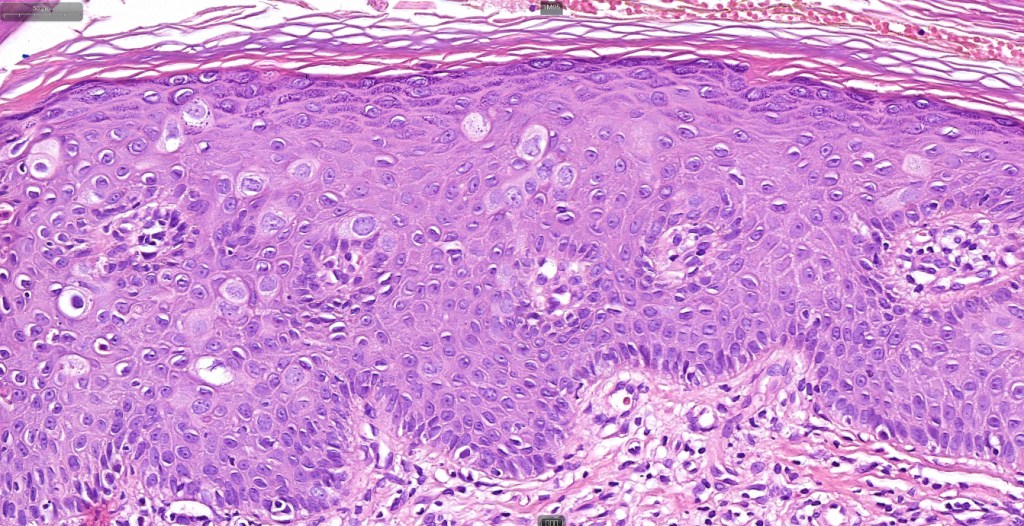

Histological features

•Hyperkeratosis, parakeratosis & acanthosis

•Full thickness dysplasia (carcinoma in situ) involving the epidermis and intraepidermal adnexal elements

•Loss of maturation, nuclear pleomorphism, marked mitotic activity +/- abnormal forms

•Dyskeratosis & apoptosis